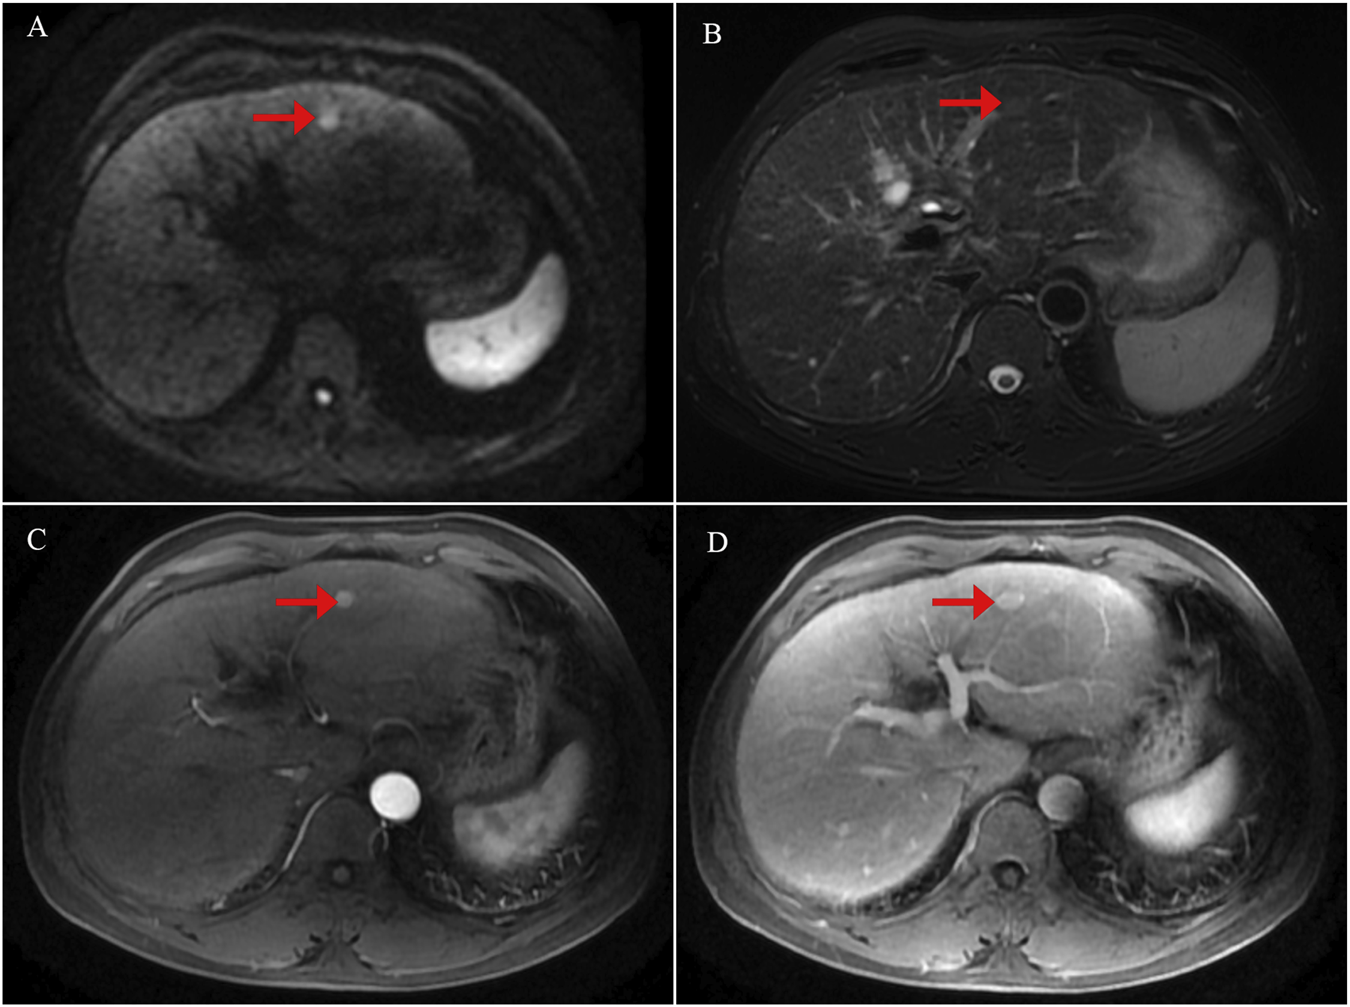

FIGURE 1

Initial contrast-enhanced liver magnetic resonance imaging (MRI) findings at the time of diagnosis. (A) Diffusion-weighted imaging (DWI) showing a focal area of restricted diffusion in the liver. (B) T2-weighted image demonstrating corresponding hyperintensity in the lesion. (C) Arterial phase of contrast-enhanced MRI revealing early enhancement of the lesion. (D) Venous phase image showing washout or delayed enhancement characteristics.